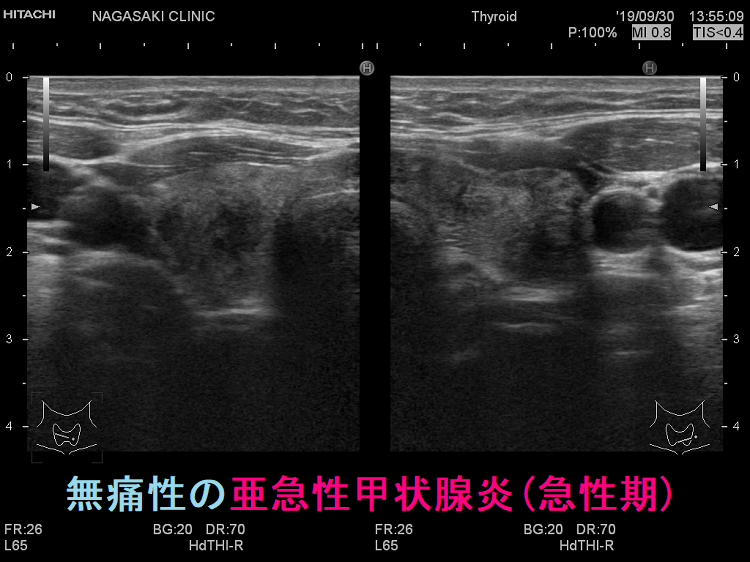

亜急性甲状腺炎の頚部痛は千差万別です。まるで痛風のごとく、触れただけで飛び上がるような痛み、蚊に刺されたほどの痛み、無痛性の場合もあります。(Thyroid. 2001 Jul;11(7):691-5.)

頸部痛を伴わない無痛性亜急性甲状腺炎(painless subacute thyroiditis)の頻度は全体の5-10%とされ、特に新型コロナウイルス感染後の報告が増えています。[Cureus. 2022 Jul 16;14(7):e26924.][Cureus. 2022 May 12;14(5):e24949.]

不思議な事に、無痛性であっても炎症が強かったり、甲状腺中毒症が強かったりします。元々、痛みに鈍感な高齢者や糖尿病患者でなくても無痛性の場合があります。

無痛性であっても、甲状腺超音波(エコー)所見はほぼ共通です。要するに、超音波(エコー)検査で即診断。